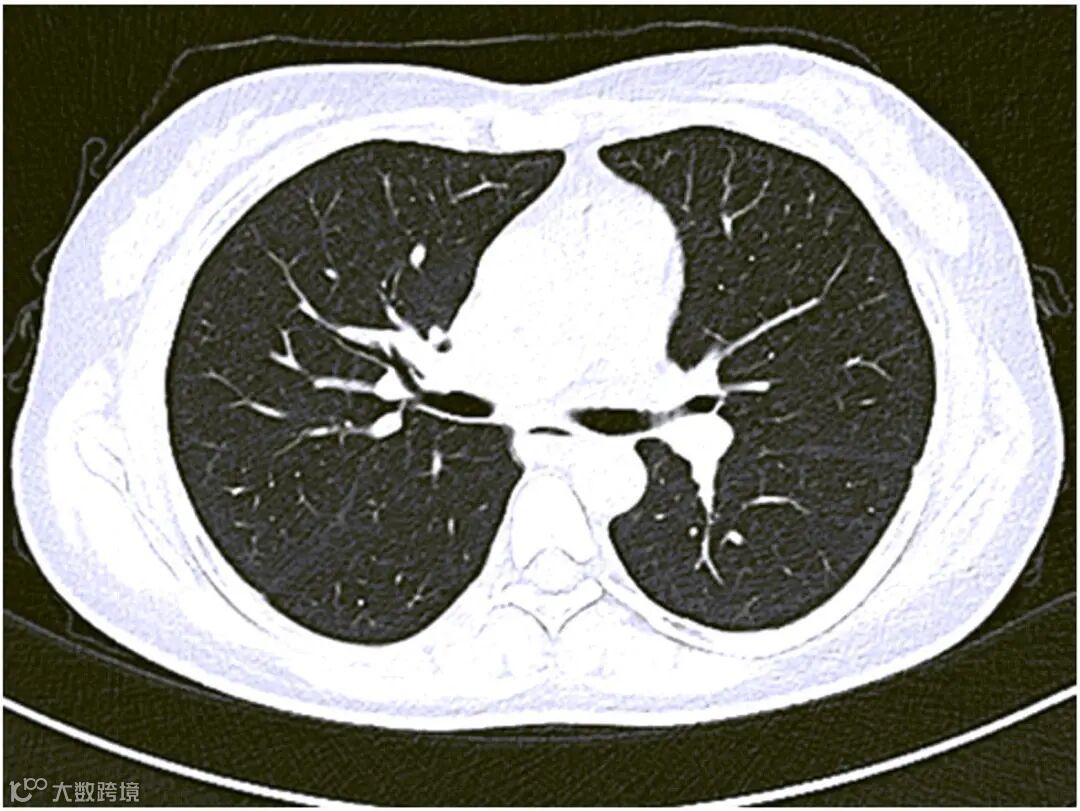

注:两肺未见活动性或间质性病变。

图1 肺部CT